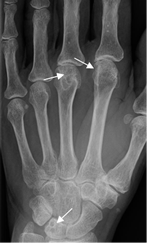

Fig 24 A. Artropatía reumática.

Rx AP. Enfermedad avanzada con osteoporosis, disminución simétrica del espacio articular y deformidad.

Fig 24 B. Artropatía reumática.

Rx AP. Enfermedad avanzada en la mano, con osteoporosis periarticular, disminución de los espacios articulares interfalángicos, radio y ulnocarpiano y fusión de los huesos del carpo.

Fig 25. Artropatía reumática.

Rx AP. Enfermedad muy avanzada, con sub y luxación de articulaciones metacarpofalángicas. Reabsorción y cambios PostQx en los huesos del carpo y el tercio distal de los cúbitos.